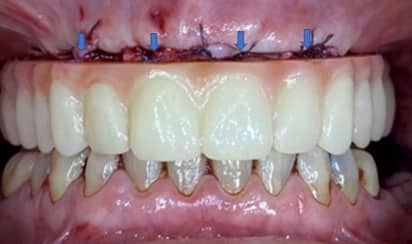

Minimally Invasive

Our EXPERIENCE and METHOD give our patients faster RECOVERY time.

Custom-Made (OUR)

Match to Existing Natural Gum Tissue

Minimal Invasive Surgery